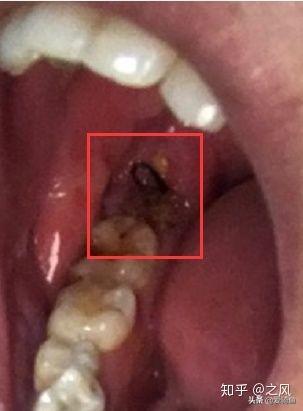

拍好片子后,去就診,房間里一個主治醫(yī)生,一個年輕女幫手,主治醫(yī)生看片子廢話不多說,安排你躺下,燈照著你,告訴你別緊張,說“緊張就別拔了”,然后打麻藥,三分鐘左右吧右下半部分臉就麻木了。然后拿一個錘子一個鑿子,砰砰砰鑿、撬起來了,雖然不疼但這陣仗會讓人緊張起來,然后醫(yī)生就會說你,”別緊張,放松,越緊張越難拔“,估計不到2分鐘一顆智齒就給拔下來了,然后半分鐘給你縫了線。 給你塞了一個止血棉讓你咬住。

黑線縫合傷口